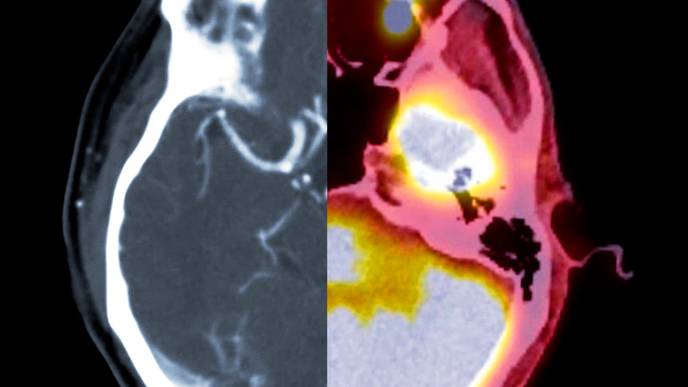

Participants who were eligible based on blood tests also underwent positron emission tomography (PET) scans, brain scans that are used to directly measure amyloid buildup in the brain. Among “plasma eligible” participants (those who met the blood test cutoff), individuals from all racial and ethnic groups were equally likely to be eligible to participate based on PET scan data. The study was just published in Alzheimer’s & Dementia: The Journal of the Alzheimer’s Association.

The researchers collected blood from each participant and calculated amyloid levels, using a liberal threshold to determine who was considered eligible for inclusion in the clinical trial. The trial requires a participant to have 20 centiloids or more of amyloid, but researchers lowered the cutoff to 11 centiloids to avoid excluding participants who might be just below the typical threshold. Centiloids are units in a standardized method of measuring amyloid plaque in the brain based on PET imaging.

Of the 4905 adults tested, 1,724 (35.1%) were “plasma eligible” to participate in a clinical trial, meaning they met the 11-centiloids blood test cutoff. Broken down by racial and ethnic group, non-Hispanic whites had the highest rate of eligibility at 38.9%. All other groups were significantly less likely to meet eligibility criteria: just 13.3% of Hispanic Blacks, 24.7% of Hispanic whites, 20.8% of non-Hispanic Asians and 24.7% of non-Hispanic Blacks surpassed the 11-centiloids threshold.

Then, the researchers collected and analyzed PET scans from the 1,724 participants who were deemed plasma-eligible for the clinical trial. All racial and ethnic groups in the study were equally likely to meet inclusion criteria based on PET scans.